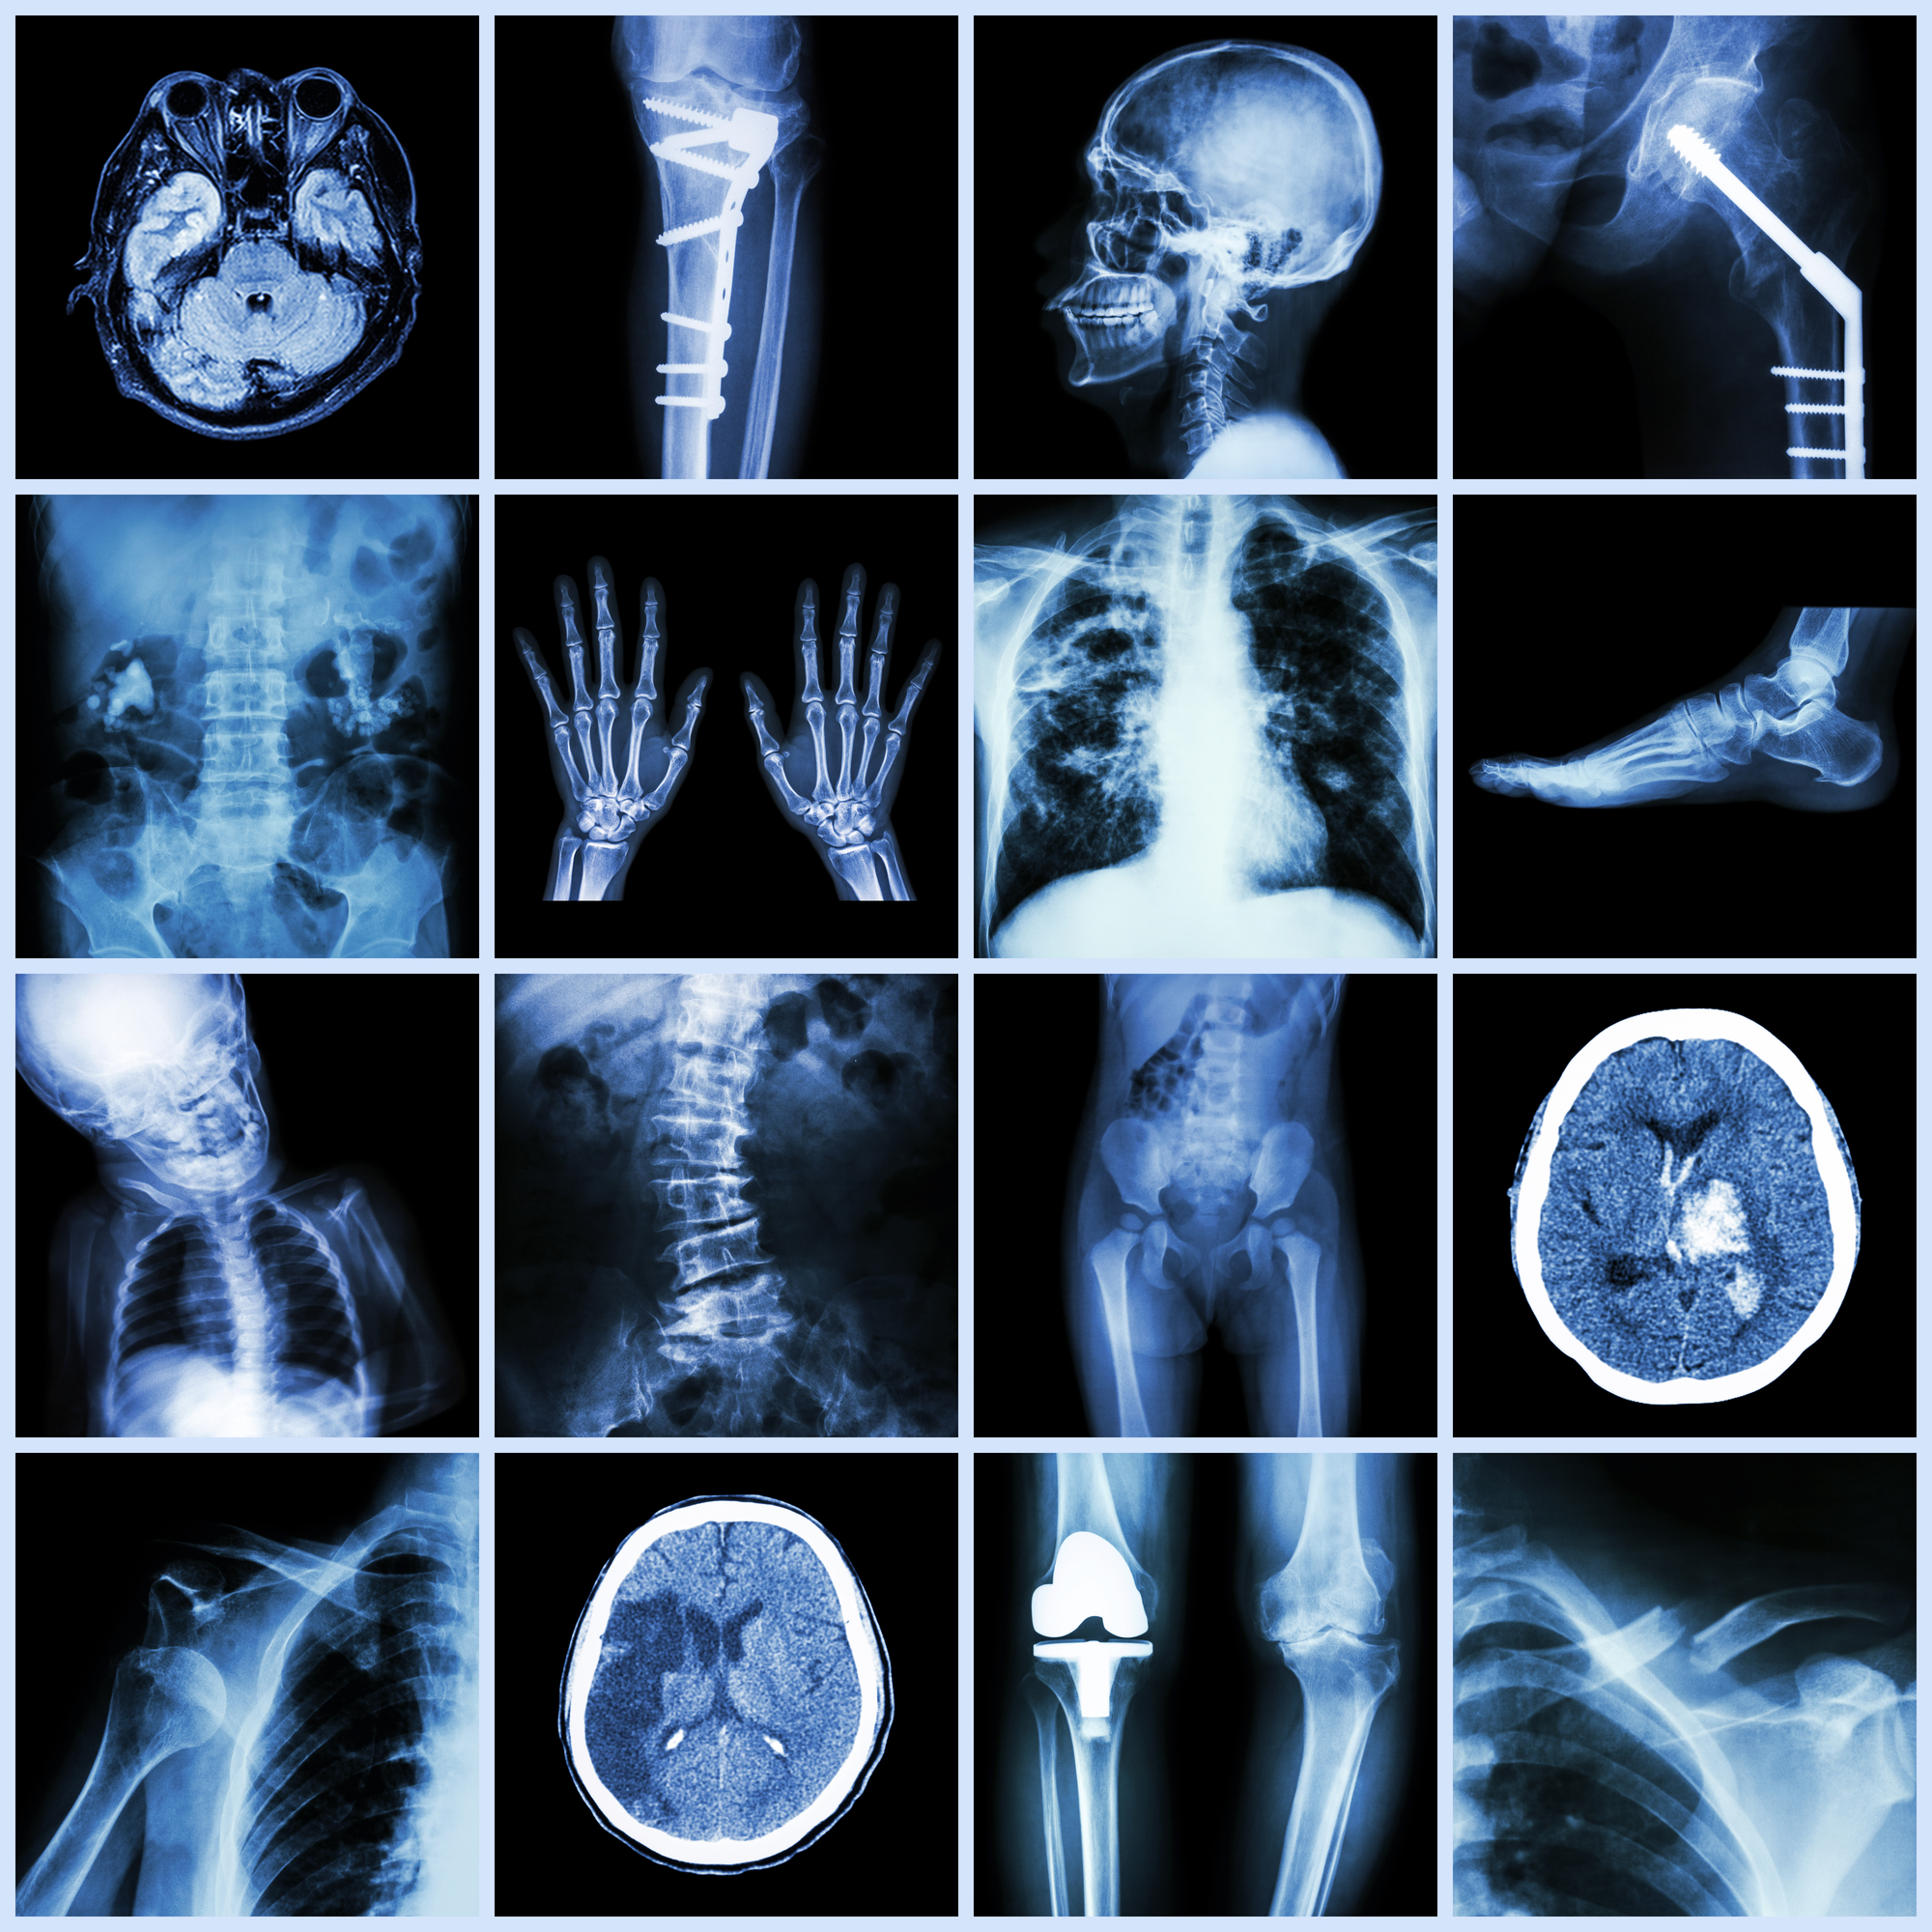

Top 5 Uses of X-rays

An X-ray is a common diagnostic procedure that is performed in nearly every hospital and outpatient center. There are many reasons why your doctor might order an X-ray. However, some are more common.

Some of the most common reasons are:

- To evaluate symptoms in the body. An x-ray can help doctors look inside the body and may help them evaluate symptoms you’re having. This is especially useful when helping to diagnose illnesses, such as pneumonia or heart problems.

- To diagnose injuries. When you have sustained sudden trauma, doctors may use an x-ray to identify injuries, such as broken bones and joint dislocations.

- To perform dental checks. Dentists often use x-rays to check the oral health of their patients. X-rays are ideal for finding cavities and tooth decay.

- To diagnose cancer. Doctors often use x-rays to diagnose and stage various cancers. They’re also used in mammograms to help detect breast cancer.

- To identify joint changes. Specialists often use x-rays to identify arthritis in elderly patients. While a typical x-ray might not work to detect joint changes, special x-rays called arthrograms can identify problems and help doctors treat arthritis.